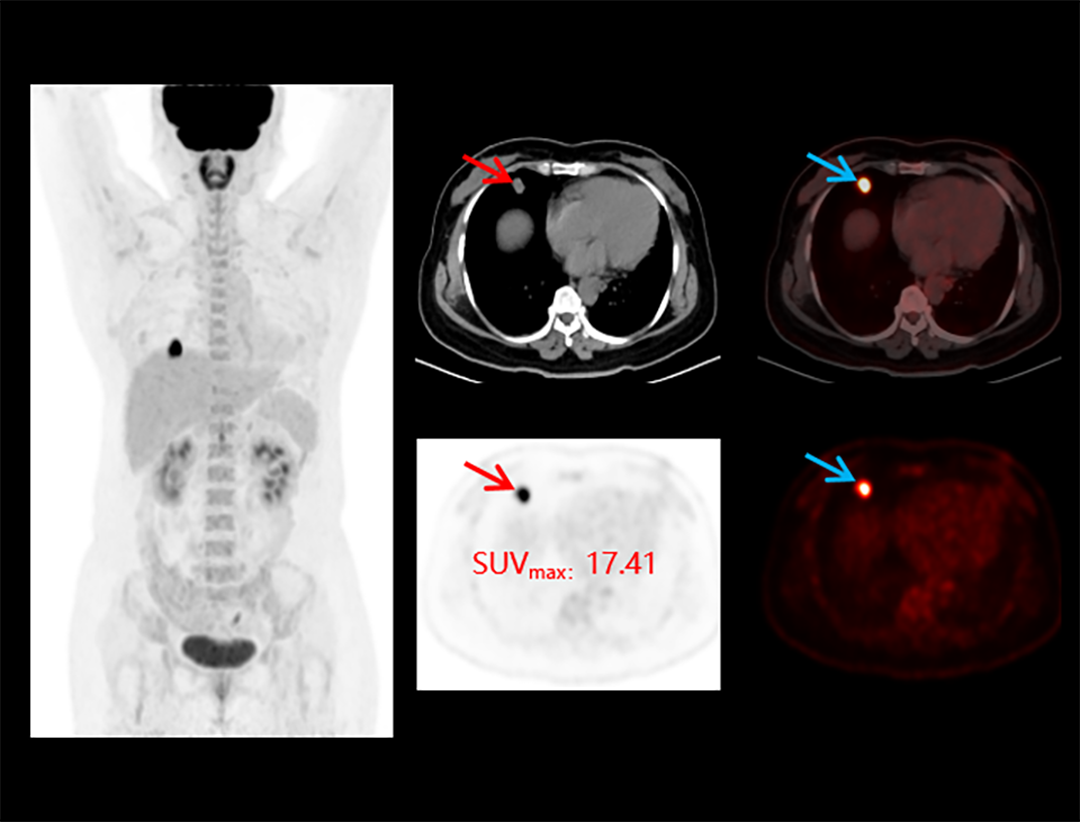

Integrated Oncology Application

The uMI 550 offers a comprehensive solution package for tumor diagnosis and post-therapeutic evaluation on the operation console.